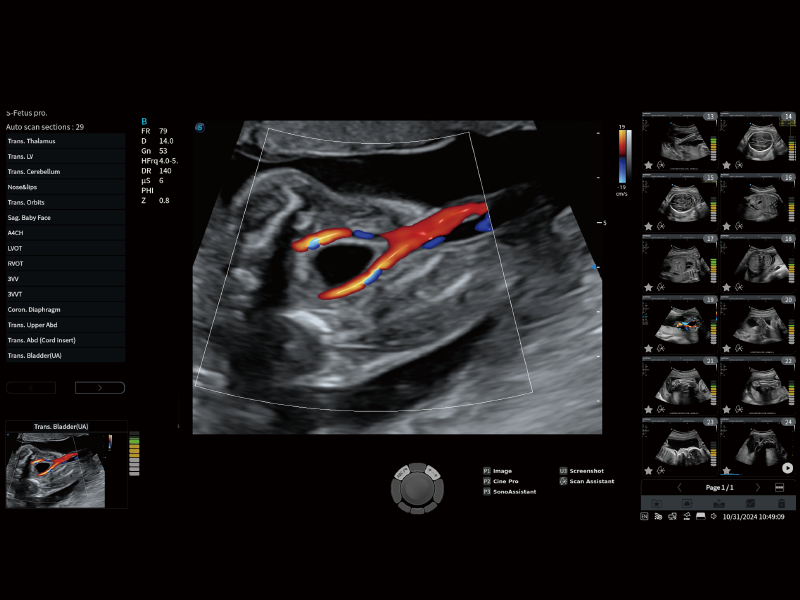

豐富的血流動(dòng)力學(xué)檢測(cè)技術(shù),可在不同醫(yī)療場(chǎng)景中高效捕捉血流信號(hào),助力臨床診療。

在傳統(tǒng)血流的基礎(chǔ)上優(yōu)化掃查和算法策略,能夠更好的抑制組織信息,提煉紅細(xì)胞運(yùn)動(dòng)信息,得到更高幀頻,高靈敏度和分辨率的血流信號(hào),還原更真實(shí)的血流動(dòng)力學(xué)。